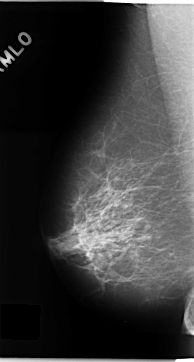

C_0133_1.RIGHT_MLO

RIGHT_CC LINES 4768 PIXELS_PER_LINE 2528 BITS_PER_PIXEL 12 RESOLUTION 50 NON_OVERLAY

RIGHT_MLO LINES 4704 PIXELS_PER_LINE 2520 BITS_PER_PIXEL 12 RESOLUTION 50 NON_OVERLAY